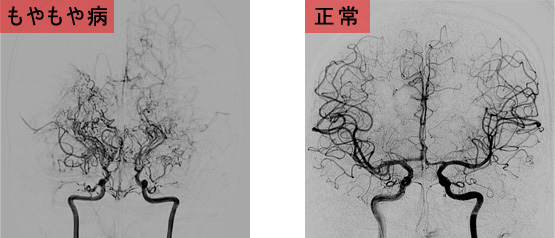

もやもや病は内頸動脈という脳全体の約2/3を栄養する血管が、進行性に狭窄・閉塞し、代償として異常な血管網の発達(もやもや血管)を認める原因不明の病気です。病気が診断されるのは、10歳以下を中心とする幼少期と30~40歳を中心とする成人期が多いとされています。

もやもや病では,通常認められる主幹動脈(太い血管)が消失している代りに,もやもやした血管(もやもや血管)が発達している。